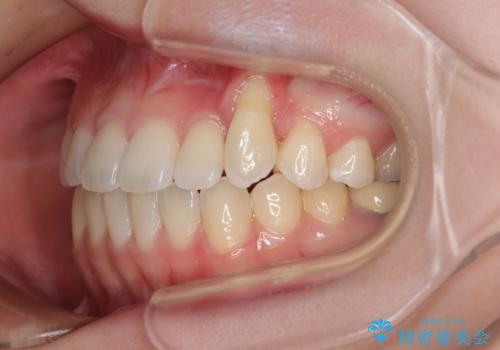

- 上顎の八重歯やデコボコを気にして来院された患者様です。

上顎歯列が狭窄していたため、急速拡大装置により上顎骨を側方に拡大しながら、ワイヤー装置にて矯正治療を行うこととしました。

上顎骨を拡大することで、八重歯やデコボコを歯列に収めることができ、下顎の歯が外に位置していた奥歯の咬み合わせも改善することができました。

スペースも短期間に獲得できるため、1年程度で治療を終えることができました。